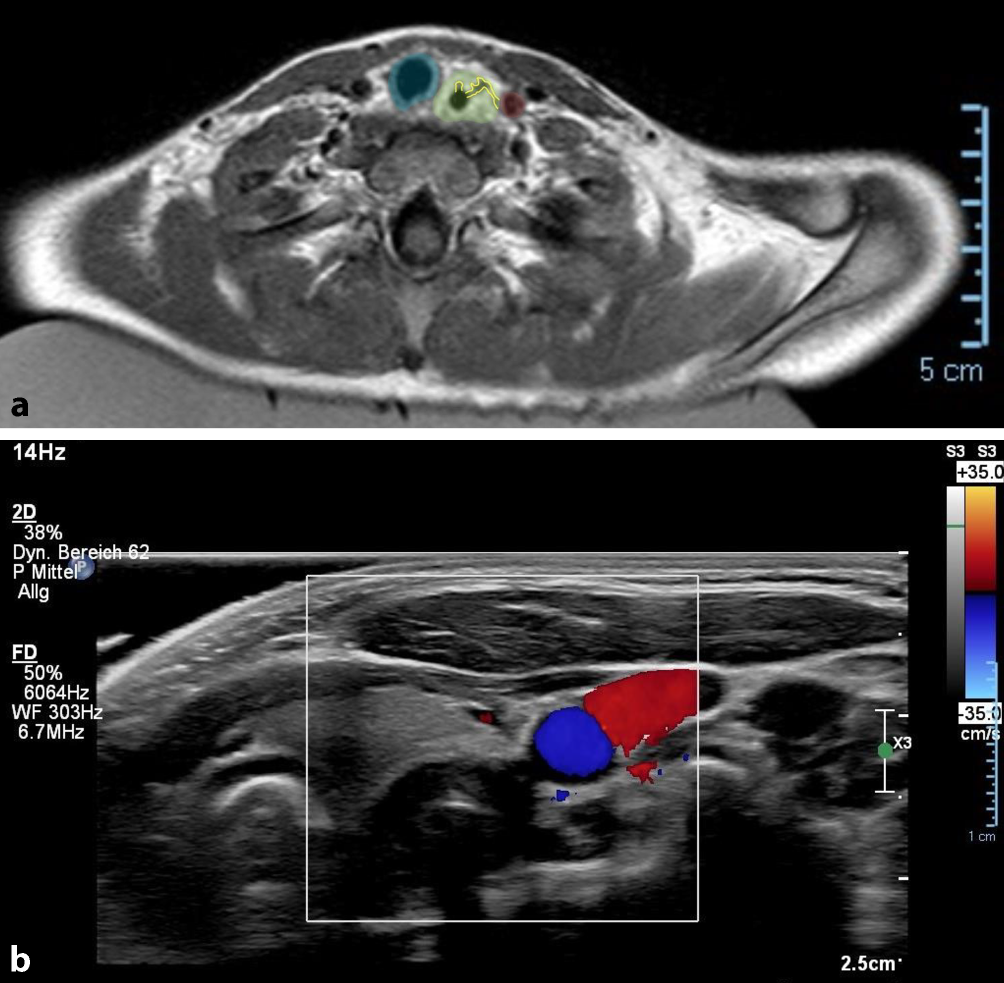

Dem Standard in unserem Kinderkrankenhaus entsprechend wurde eine MRT-Untersuchung nach 2 Tagen durchgeführt, um die typische Panösophagitis sowie mögliche, sich darin ausbildende Fistelgänge, darzustellen. Hierbei wurde ein entzündlich-ödematös aufgetriebener Ösophagus mit gangbildenden Ulzerationen bis zur Wand der Arteria carotis communis (ACC) links gezeigt. Sonographisch konnte keine eindeutige Barriere mehr zwischen diesem Gang und der ACC dargestellt werden (Abb. 1).

Abb. 1

a MRT präoperativ. Trachea (blau), ödematöser Ösophagus (grün) mit 2 gangbildenden Ulzerationen (gelb), von denen einer bis in die Nähe der ACC (rot) reicht. b Farbkodierte Duplexsonographie: Ösophaguswand ohne erkennbare trennende Strukturen zur ACC (Farbduplex, blau)